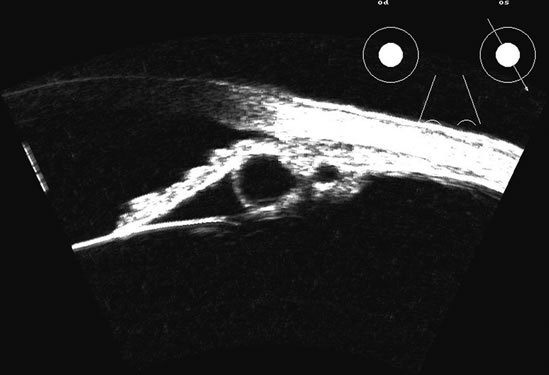

The choroid, like the retina, is highly reflective and may resemble the retina when detached. Its thickness, which includes the retina, Bruch's membrane, and the choriocapillaris (tunica ruyschiana) is not usually differentiable when measured with routine ultrasound;12 however, it may be measured with digital techniques.18 Anatomically, the choroidal elevation is usually a smoothly round, convex surface, limited posteriorly by the vortex veins and anteriorly at any point up to the base of the iris (Fig. 17). The choroidal space should be examined for echoes (blood) or a clear zone, as seen with effusion or the serous part of a hemorrhage. In evaluating membranes from retina or choroid, it is always helpful to repeat the examinations at a later time.

Fig. 17. This patient with a Molteno tube was treated for glaucoma. The top 50 MHz B-scan clearly shows the Molteno Tube (arrow). The bottom 10 MHz B-scan of the same patient demonstrates a choroidal detachment (large arrow) with associated posterior retinal detachment (small arrow). Choroidal elevations are typically convex, highly reflective surfaces with posterior limitation at the vortex vessels. Retina will always attach at the optic nerve. Choroidal elevations are often noted in several quadrants, as seen here.